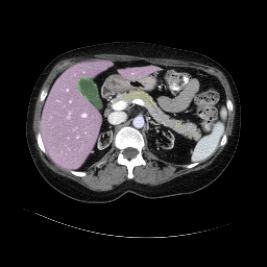

Integrating high-level semantically correlated contents and low-level anatomical features is of central importance in medical image segmentation. Towards this end, recent deep learning-based medical segmentation methods have shown great promise in better modeling such information. However, convolution operators for medical segmentation typically operate on regular grids, which inherently blur the high-frequency regions, i.e., boundary regions. In this work, we propose MORSE, a generic implicit neural rendering framework designed at an anatomical level to assist learning in medical image segmentation. Our method is motivated by the fact that implicit neural representation has been shown to be more effective in fitting complex signals and solving computer graphics problems than discrete grid-based representation. The core of our approach is to formulate medical image segmentation as a rendering problem in an end-to-end manner. Specifically, we continuously align the coarse segmentation prediction with the ambiguous coordinate-based point representations and aggregate these features to adaptively refine the boundary region. To parallelly optimize multi-scale pixel-level features, we leverage the idea from Mixture-of-Expert (MoE) to design and train our MORSE with a stochastic gating mechanism. Our experiments demonstrate that MORSE can work well with different medical segmentation backbones, consistently achieving competitive performance improvements in both 2D and 3D supervised medical segmentation methods. We also theoretically analyze the superiority of MORSE.